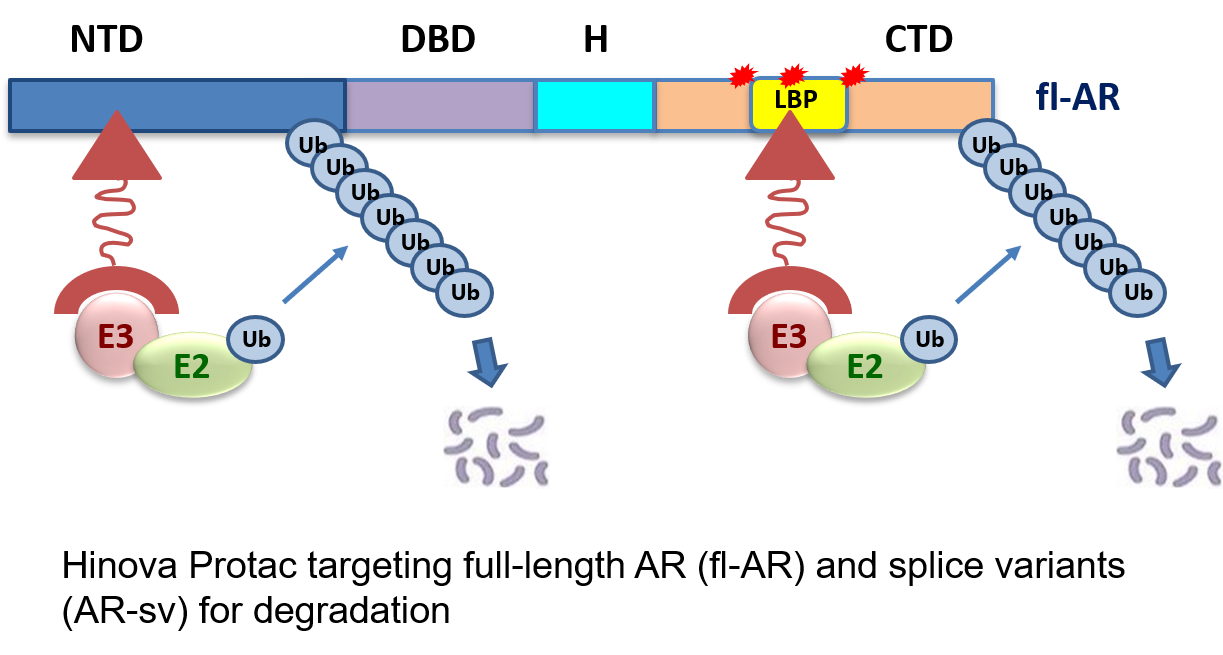

PROTAC Targeted Protein Degradation(TPD)Platform

Competitive Advantages of Hinova PROTAC Platform